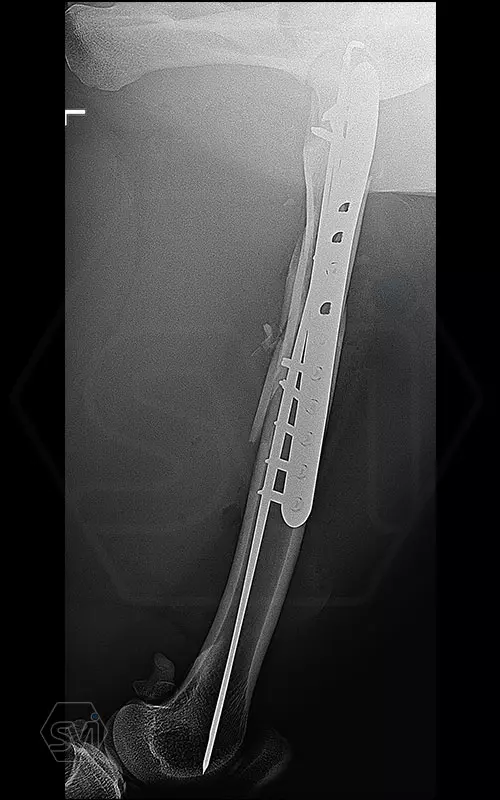

The 9-year-old female cheetah broke her leg so miserably near the femoral neck during a regrouping. Here again, the combination of the intramedullary pin and polyaxial lockin plate mentioned in the previous post was used to fix the fracture. During the screw insertions into the proximal piece, the polyaxiality came in really handy, we were able to avoid the 2.5 mm K-nails with the long screws. I hope the 14-hole 12 * 4 mm wide polyaxial plate (which could have been longer…) will be long enough, with a mix of 4.0 and 3.5 mm screws for maximum stability. From below, screw 6 is a cortical screw that secures a larger contralateral fragment as a lag screw.

Thus, 3 screws of different thicknesses (3.5 and 4.0 polyaxes) and shapes (AO screws) were placed in the plate, while ONE screwdriver was used because each has a hex head.